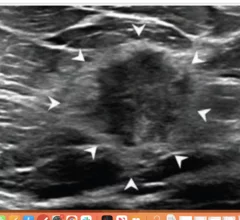

Ultrasound, also referred to as sonography or diagnostic ultrasound, uses high-frequency sound waves to visualize soft tissue. Ultrasounds are frequently ordered to measure fetal anatomy during pregnancy, check for blood clots and to guide needle biopsy procedures of the breast, abdomen and pelvis. The imaging modality does not use any radiation to create images. Find news specific to cardiac ultrasound (echocardiography).